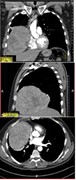

Primary mediastinal dedifferentiated liposarcoma resected by lateral thoracotomy with video-assisted thoracoscopic surgery

Kazutoshi Hamanaka and others

Journal of Surgical Case Reports, Volume 2016, Issue 1, January 2016, rjv163, https://doi.org/10.1093/jscr/rjv163